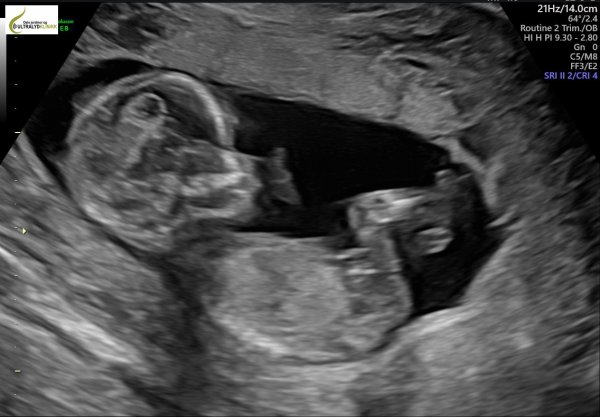

Så fint UL bilde![]()

Tusen takkDet var en enorm lettelse å se lillegutt sprelle inni der

Blir nesten like overrasket over at de finner bebis på hver UL

og like lettet over at alt stemmer hver gang